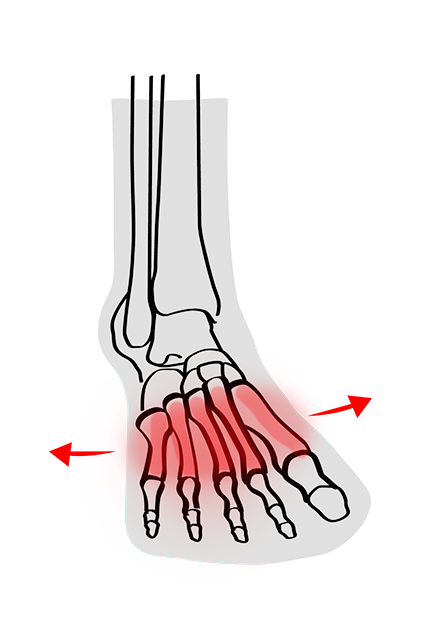

Splay Foot is challenging to live with, to say the least! The condition can affect one or both feet and often leads to various issues and symptoms that can interfere with daily activity and quality of life.

Those who suffer from Splay Foot will notice a reduction in their quality of life due to the pain and discomfort caused. If not treated, the whole body can become impaired due to the wrongly positioned placement of the foot.